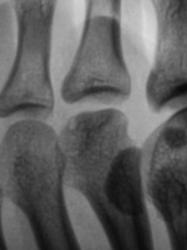

Пациент направлен на исследование стопы врачом хирургом с диагнозом - "Перелом?". Из общения с пациентом возникло сомнение о "наличии травмы". Произведена рентгенография стопы в стандартных проекциях.

При анализе рентгенограммы "данных за перелом" не выявлено. Возникли сомнения по поводу суставной поверхности головки 2 плюсневой кости. ВАШЕ МНЕНИЕ УВАЖАЕМЫЕ КОЛЛЕГИ?

Келлер 2

Я согласен с Вами, и допускаю наличие остеохондропатии, но затрудняюсь с определением стадии.

Действительно, похоже на Келера в стадии исхода.

на остеохондропатию. Болезнь Кёлера2.